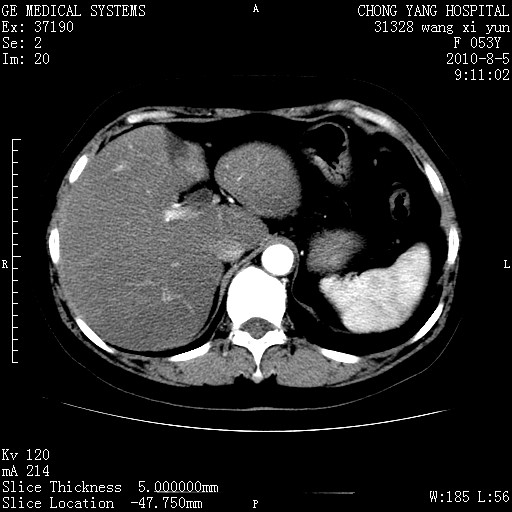

标题: CT28214:F41Y 血尿二十天,建议盆腔平扫加增强。

1)考虑肝左叶胆管细胞癌。2)脂肪肝。